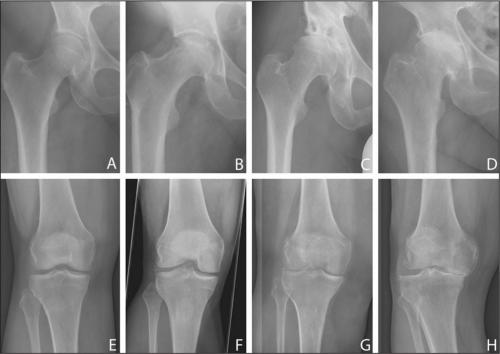

Стадии артроза коленного сустава. Обратите внимание на сужение суставной щели.

Все медикаментозные средства эффективны лишь—, но бессильныи IV. Если в патологию вовлечены не только суставы, но и кости, никакой препарат не поможет. В этом случае избавиться от хронических, трудностей при ходьбе, ограниченной подвижности суставов и других неприятных симптомов можно только с помощью операции.

Существуют три поколения хондропротекторов. К первому относятся препараты, изготовленные из натуральных компонентов (,), ко второму – монопрепараты (, Структум, Артрадол), к третьему – комбинированные средства (, Артра, Глюкозамин-Хондроитин Плюс, Кондронова). Наиболее эффективны лекарства III поколения.